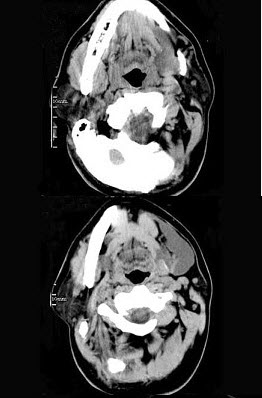

男,32岁,左侧下颌部肿块,CT如图所示,最可能的诊断是()。

A、造釉细胞瘤

B、颌骨囊肿

C、鳃裂囊肿

D、颈部淋巴管瘤

E、舌下腺囊肿

正确答案:

E